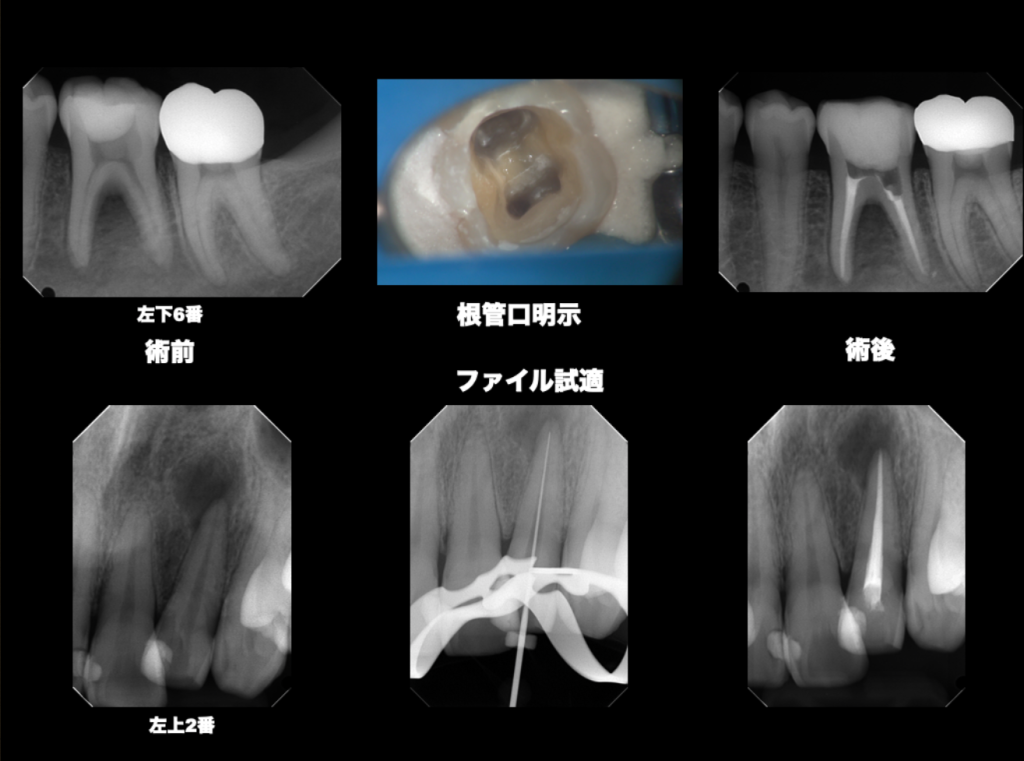

マイクロスコープ

肉眼では確認できない根管内部を

明視野下かつ高倍率で見る

精密根管治療に必要不可欠

「精密」な根管治療

マイクロスコープやCTなど最先端の設備を駆使して、肉眼では見えない根管の微細な構造に至るまで確実に把握。精度を極めた治療で、不必要な削除を避けて、できる限り歯を残します。

②マイクロスコープによる精密根管治療

根管は非常に細く複雑であり、肉眼では確認が困難です。

当院では、すべての根管治療に対して、必ずマイクロスコープ下で実施しております。

最大20倍の拡大視野によって、感染源を一つ残らず処理することで、再発リスクを抑えています。